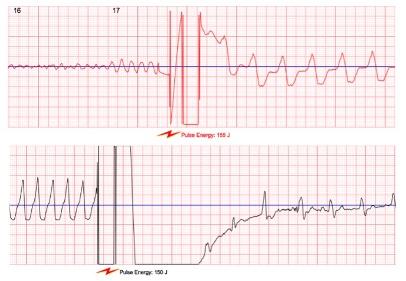

Abbildung 3: Die Abbildung zeigt im linken Streifen Kammerflimmern und im rechten Streifen eine Kammertachykardie, die jeweils durch die Schockabgabe der Defibrillations-Weste (siehe kleines Blitzsymbol), beendet und in einen normalen Rhythmus übergeführt werden.